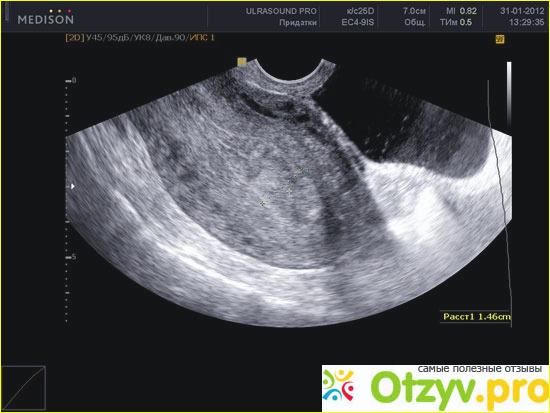

Ультразвуковое обследование матки

В настоящее время существует достаточно большое количество методов исследования женской половой сферы и среди них ультразвуковой метод является далеко не последним. Наоборот, он применяется очень часто и является достаточно информативным и показательным во многих планах. Гинекологи по этой процедуре могут поставить довольно точный диагноз, особенно если применяется современная аппаратура.

Наиболее часто проводится ультразвуковое обследование при изучении беременности, подозрении на внематочную беременность или ее приостановление (так называемая замершая беременность). Очень информативно ультразвуковое обследование при выявлении разного рода новообразований в матке – полипов, миоматьозных узлов, поликистозов яичников. Многие другие заболевания также часто выявляются при проведении УЗИ, правда порой необходимо в данном случае применение дополнительных методов.

Проведение диагностики при помощи ультразвука имеет разную информативность в зависимости от фазы менструального цикла. Желательно проводить исследования на первой фазе месячных, когда оболочка внутренняя наиболее истонченная и в ней наиболее легко выявить какие-либо вкрапления и новообразования. Очень важным моментом является ультразвуковое исследование области шейки матки. Если хоть как-то изменена структура этого места, то это должно насторожить гинеколога, поскольку при этом может иметь место воспалительный процесс, а то и вообще это может указывать на возможные новообразования. Наиболее распространенное заболевание шейки матки – это ее эрозия, которая может протекать как по доброкачественному, так и злокачественному типу. Ну а выявление новообразования, в частности опредеоение его формы можно только с применением ультразвука. Важно также проведение ультразвукового обследования при беременности, поскольку это указывает на то как протекает процесс беременности и имеются ли какие-либо отклонения от нормы.